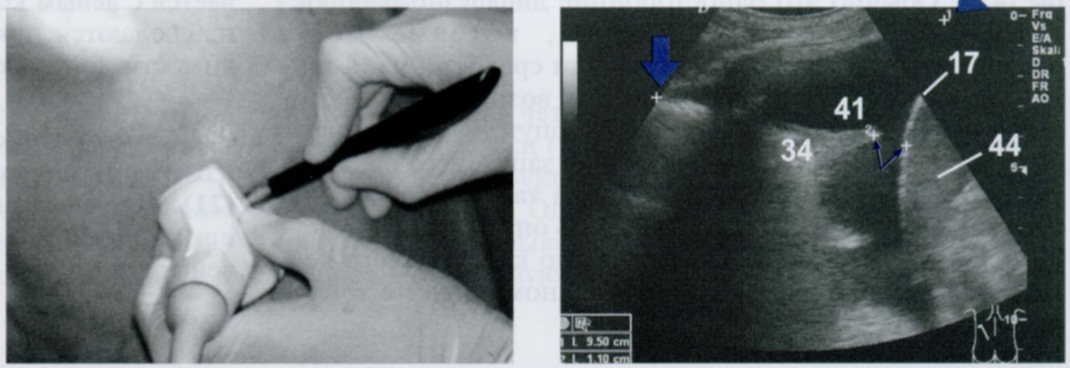

УЗ-изображение показывает распространение эхонегативного (черного) выпота (41) над диафрагмой (17) и селезенкой (44), окружающего нижний край легкого (34).

Для количественной оценки объема выпота в плевральной полости проводятся следующие вычисления. Вначале определяется максимальное расстояние от краниальной границы выпота (вертикальная стрелка) до каудальной (косая стрелка), ограниченной реберно-диафрагмальным синусом (в данном случае 9,5 см).

Затем определяется минимальное расстояние между легким (34) и диафрагмой (17) (в данном случае 1,1 см).

Чтобы рассчитать примерный объем выпота (в мл), сложите оба расстояния, и сумму умножьте на 70. В приведенном примере объем выпота составляет 9,5 + 1,1= 10,6 × 70= примерно 740 мл.